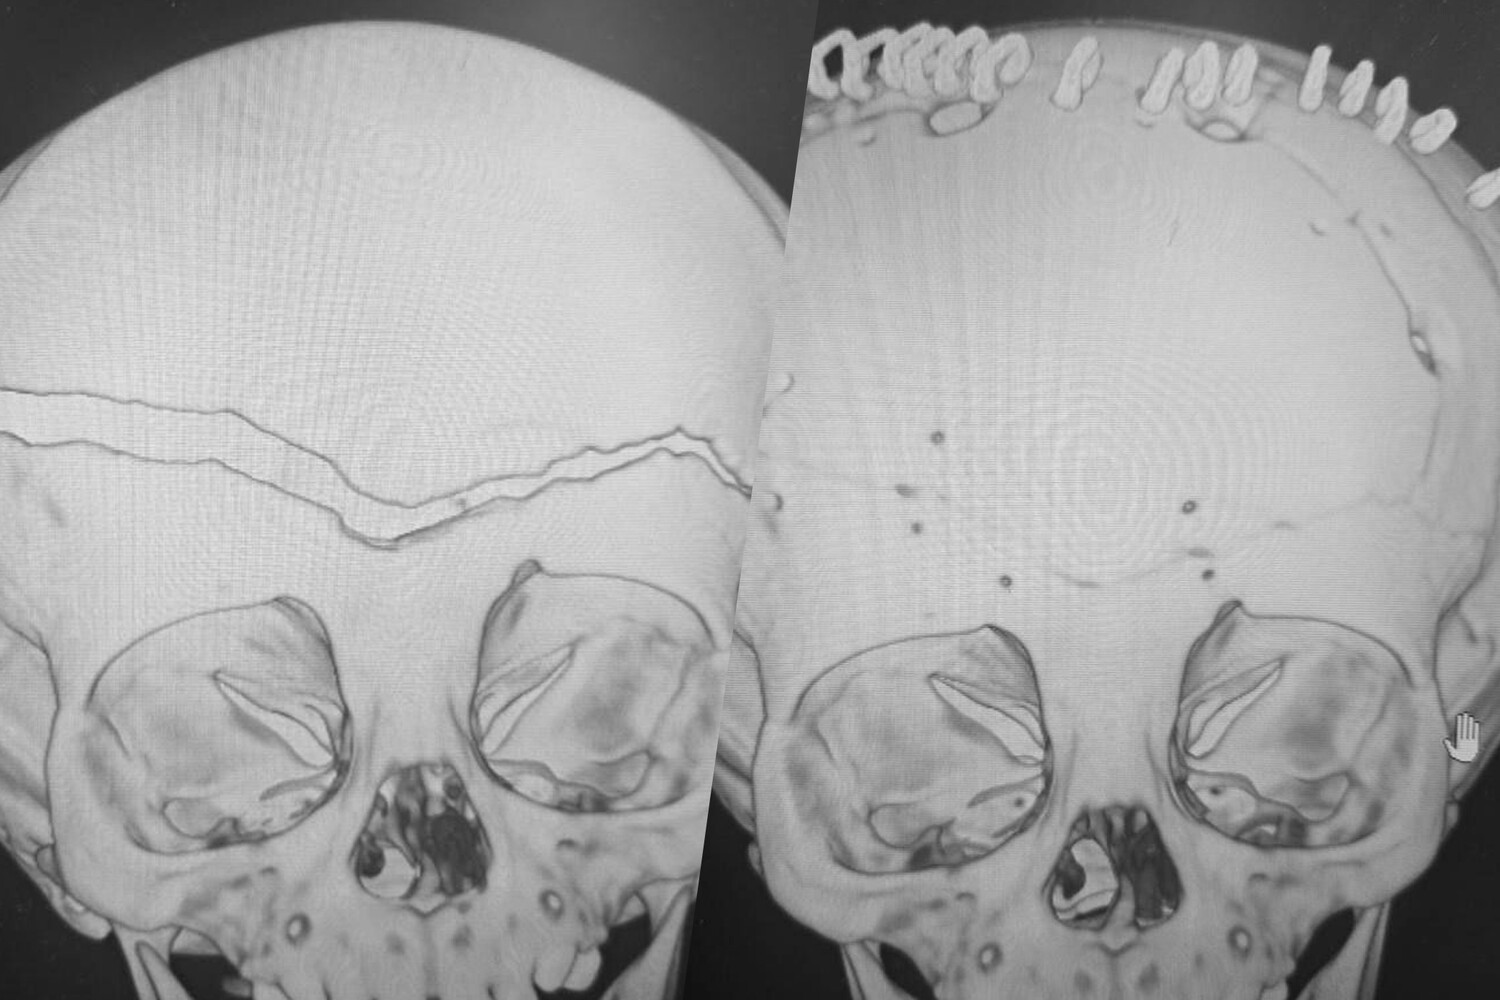

«У ребенка была гигантская эпидуральная гематома и линейный перелом лобной и теменной костей с расхождением линии перелома до 1,5 см», — рассказал заведующий нейрохирургическим отделением ВКБ №2 Сергей Моисеенко, добавив, что у его коллега на счету была каждая минута.